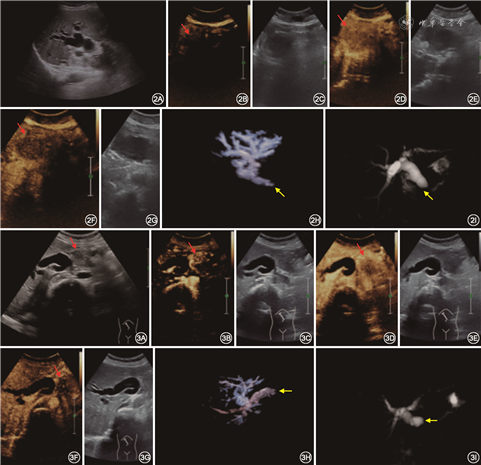

69例低位梗阻的患者中有胆管癌20例,胰腺癌14例,多发性骨髓瘤胰腺侵犯1例,壶腹癌5例,胆管炎5例,胰腺炎1例,十二指肠乳头炎6例,胆管结石17例。通过US确诊39例,误诊30例,误诊率43.5%(30/69),其中4例胆管泥沙样结石呈不伴声影的规则低及等回声团块误诊为炎症,2例胆管泥沙样结石呈与管壁不清的不规则肿块误诊为肿瘤,5例炎症(胆管炎3例,十二指肠乳头炎2例)误认为肿瘤,1例炎症误诊为泥沙样结石,15例肿瘤(胆管乳头状癌1例,胆管壁浸润癌4例,胆管结节状癌4例,胰腺癌4例,壶腹癌2例)呈形态尚规则,胆管扩张不明显误认为炎症,3例肿瘤(胆管乳头状癌2例,胆管结节状癌1例)呈类圆形管腔内略高回声团块误认为泥沙样结石。通过CEUS确诊57例,误诊12例,误诊率17.4%(12/69),其中4例炎症(胆管炎2例,十二指肠乳头炎2例)因为胆管积气和肠道气体干扰且增强模式与恶性病变相近误诊为肿瘤,8例肿瘤[胆管壁浸润癌2例,胆管结节状癌2例,胰腺癌2例,多发性骨髓瘤侵犯胰腺1例(图2),壶腹癌1例]因为病灶强化模式或梗阻胆管壁连续性与良性占位相似误诊为炎症。通过DCUS确诊59例,误诊10例,误诊率14.5%(10/69),其中5例胆管炎性改变(胆管炎2例,十二指肠乳头炎3例)因胆管扩张明显、断端不齐、管壁毛糙误诊为胆管肿瘤,5例肿瘤(胆管壁浸润癌2例,胆管结节状癌1例,胰腺癌1例,壶腹癌1例)未表现出典型恶性胆道梗阻(图3)增强模式、管壁连续性与良性病变相似且断端形态平整、“枯树枝”样走行误诊为炎性病变(表3)。

US对肝内胆管低位梗阻诊断准确率仅56.5%,与Blackbourne及周静等[8, 9]报道相似,主要原因是胆管内泥沙样结石误诊为肿瘤和炎症,同时良恶性病变也只能通过二维切面上病灶的形态及与周围组织器官关系等生物学行为初步判断。病灶回声和周围组织相差不大、胆道扩张不明显、受患者消化道气体影响等因素均不利于US对胆道低位梗阻的定性评估。CEUS对胆道低位梗阻诊断准确率为82.6%,与之前文献[5]报道相比准确率较低,主要是因为一些胆管炎致管壁增厚性狭窄和较小的胆管不全梗阻,同时病灶易受周围胃肠道气体干扰,显示欠佳,增强模式很难观察。低位胆道梗阻的CEUS增强模式和增强形态在胆道低位梗阻诊断中差异有统计学意义(P<0.05),但一些恶性肿瘤或者良性占位增强模式存在交叉,可能由于部分肿瘤滋养血供来源复杂或乏血供,增强模式不典型,本研究中管壁浸润型和结节型胆管下段来源肿瘤由于其很少伴胆管明显扩张及很少突入官腔内团块型生长,很难与局限性管壁增厚性炎症鉴别。某些良性病灶由于血供丰富常常动脉期表现为高或等增强,静脉期仍未见明显消退,可能和病灶内部大量新生毛细血管有关(图2)。邓小红等[10]利用超声双重造影发现其对直肠癌术前T分期与病理的总符合率为73.6%(53/72)。本研究发现DCUS结合了病灶内部本身活性和外部侵袭特征的生物学特点做出综合判断,大大提高了诊断准确率。原因可能是恶性肿瘤沿着胆管壁蟹足样生长,往往对胆管本身造成一定破坏,与胆管壁分界不清,常常形成重度不规则狭窄,扩张胆管往往呈“软藤”样(图3);而良性病变由于术后炎性水肿致胆管壁环形均匀增厚,管腔为轻度向心性狭窄,胆管结石则由于机械性滑动,形成与管腔相似的铸型,梗阻胆管断端光滑多呈半圆形充盈缺损,同时良性狭窄由于其生物惰性往往梗阻程度较轻,造成轻、中度渐进性胆管扩张,病灶侵袭胆管长度也比较局限。DCUS分级系统在胆管低位梗阻各级间的差异充分说明其对低位胆道梗阻定性诊断的意义,级别越高意味着恶性风险程度越高。MRI+MRCP和DCUS的ROC曲线显示二者诊断胆道低位梗阻的AUC分别为0.897和0.906,差异无统计学意义(P=0.522),说明DCUS和MRI+MRCP对胆道低位胆道梗阻均具有定性诊断价值,当等级为2.5级时,DCUS的灵敏度、特异度为77.5%、93.1%,MRI+MRCP的灵敏度、特异度为87.5%、82.8%,二者较为相近。MRCP属于间接胆道成像,对胆管狭窄的灵敏度和特异度较低(67%)[11]。